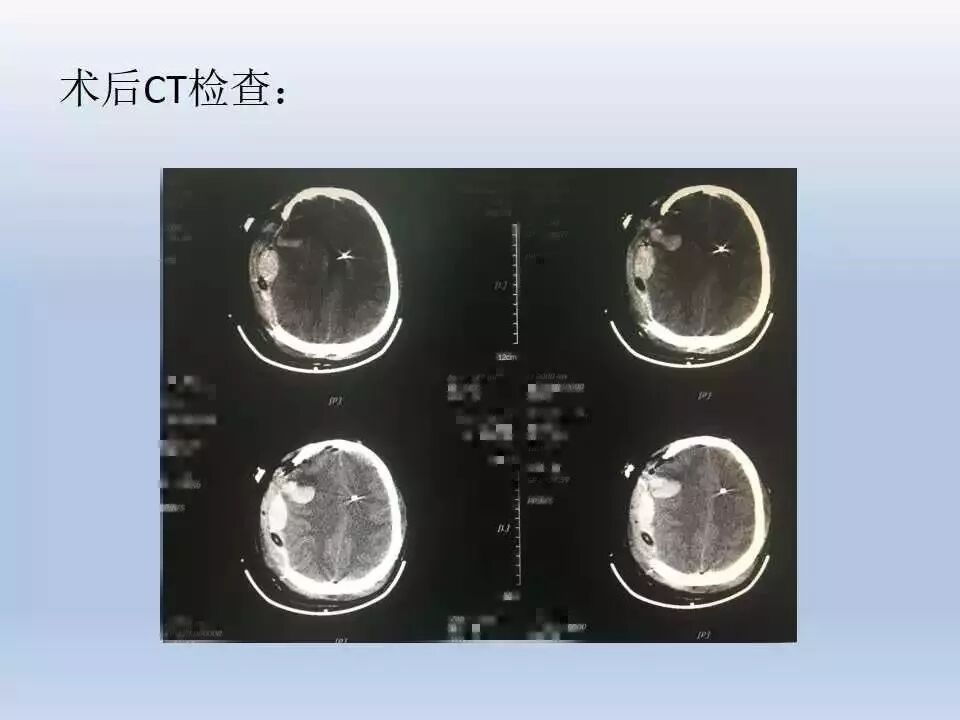

该患者经紧急抢救后,立即进行标准大骨瓣开颅减压、清除血肿,术后ICP监测、镇静镇痛、亚低温治疗、气管切开等一系列的规范化治疗措施。术后早期开展康复治疗。术后约2月早期进行颅骨修补,避免去骨瓣减压所带来的并发症。最终取得比较好的治疗效果。这充分说明规范化治疗有助于提高颅脑创伤的治疗效果。